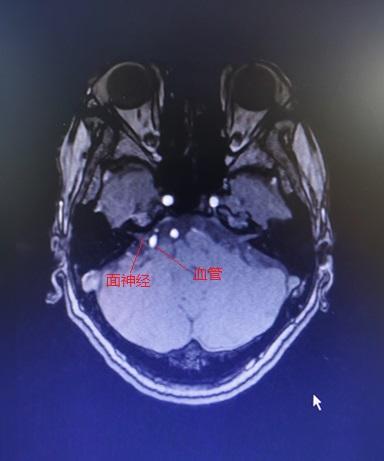

这是MRI增强,可见强化的白色血管压迫面神经